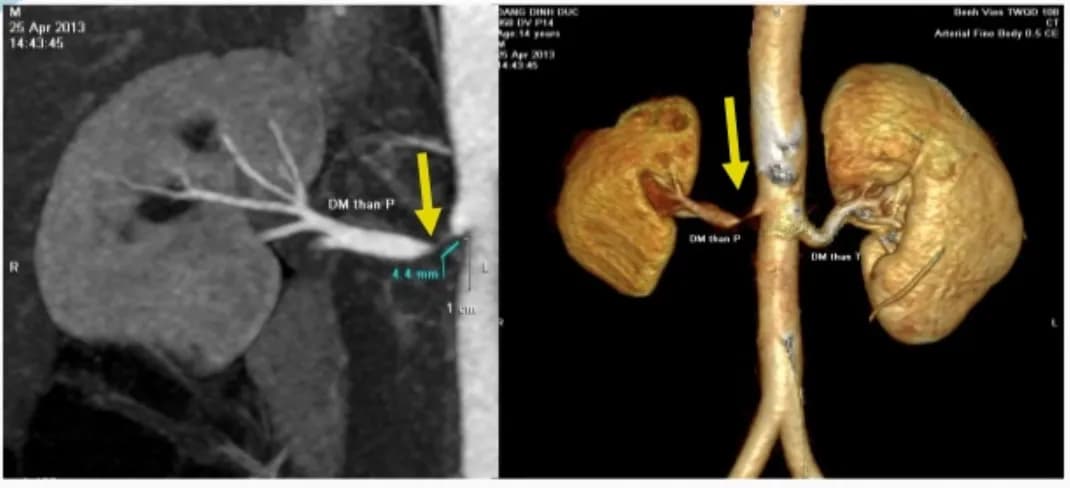

Các dạng hẹp động mạch thận

Hẹp động mạch thận là tình trạng hẹp lòng động mạch thận, làm giảm lưu lượng máu đến thận. Nguyên nhân chủ yếu do xơ vữa...